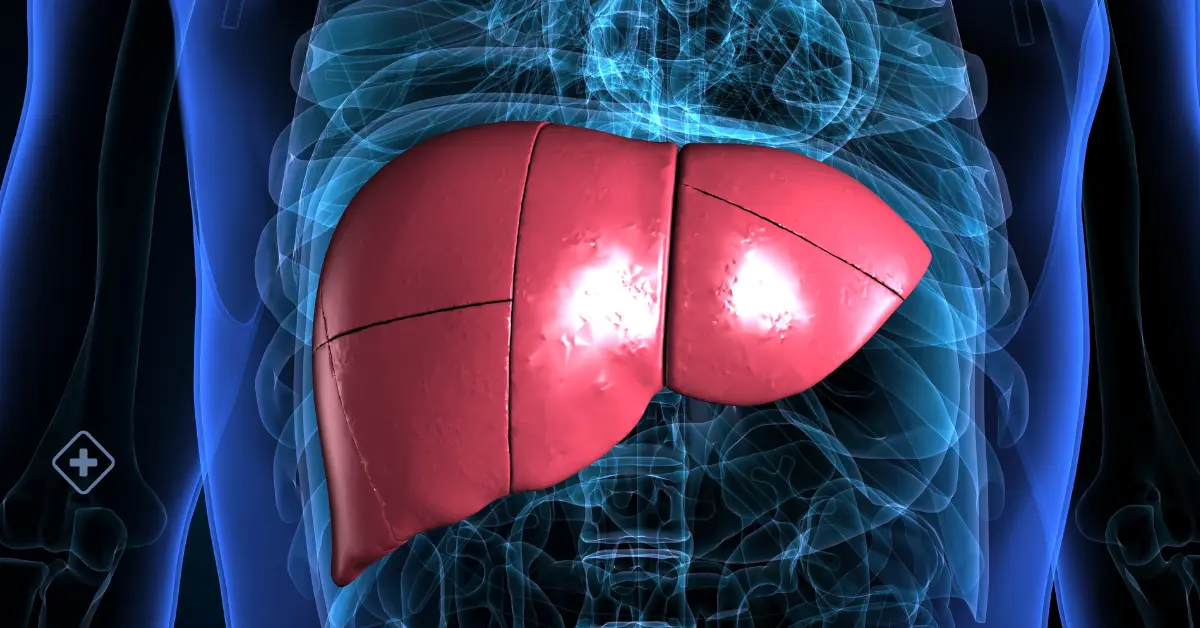

Cirrhosis

Cirrhosis can be caused by a variety of diseases and risk factors